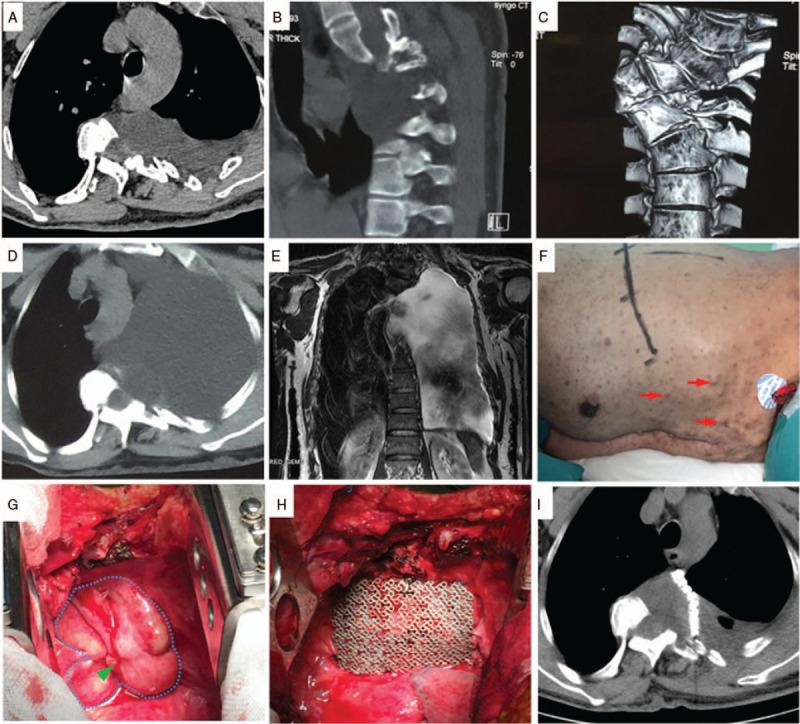

巨大前侧脑膜膨出的个体化管理——病例系列

Anterior spinal meningoceles are rare neuroanatomic abnormality formed by protrusion of the spinal meninges through a defect in the vertebral column. Presently, therapeutic options for anterior spinal meningoceles are still controversial. The objective of this study is to discuss the individualized management of giant anterior spinal meningoceles.

PATIENT CONCERNS AND DIAGNOSES

We analyzed 4 patients with anterior spinal meningoceles between 2007 and 2014 in our department by retrospective chart review, two of whom were anterior sacral meningoceles (ASMs), and another2 were intrathoracic meningoceles (ITMs).

INTERVENTIONS AND OUTCOMES

Patients mainly presented with compressive symptoms including rectal irritation, dyspnea (patient 3) and fixed neurologic deficits (patient 4). Three out of 4 patients received surgical treatment, one of which underwent reoperation. After surgery, meningoceles in 1 patient completely disappeared. Two patients acquired the stability of the size of the meningoceles.

LESSONS

Management of anterior spinal meningoceles often requires precise treatment based on the different conditions of each patient. Surgical intervention has been proposed for the treatment of symptomatic anterior spinal meningoceles. The goal of surgery is to safely disconnect the linkage between the cyst and CSF from subarachnoid space to prevent further enlargement of the cyst or reaccumulating of cystic fluid.